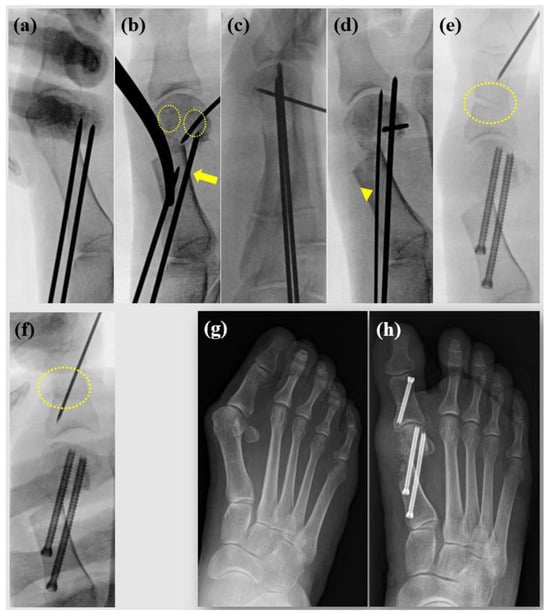

Complications were present in one patient who showed screw pull-out during follow-up, with favorable functional and radiographic outcomes. Two patients presented recurrent hallux valgus: one patient reported satisfactory surgical results along with significantly improved pain scores, while the other reported disappointing results. An example case is depicted in Figure 6.

Figure 6. Case example of female, 35-year-old patient. (a) Preoperative radiographs show moderate hallux valgus deformity; (b) 6 weeks following surgery, bunionette correction was also performed simultaneously; (c) 2 years following surgery.